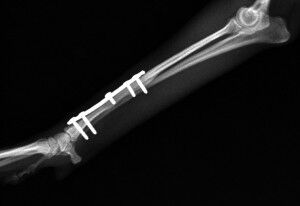

こんばんは、フジタどうぶつ病院です。今日はトイ・プードルの橈尺骨骨折の治療についてご報告させて頂きます。トイ・プードルは脚が長く、骨が細いので非常に骨折が多い犬種です。椅子やソファーから降りた時に折れたり、中には飼い主さんの後ろを歩いていて気づいたら脚を挙げていて病院でレントゲンを撮ったら折れていた、ということもあるようです。今回の症例報告のワンちゃんは椅子から降りた時に折れてしまったようです。下の写真が病院に来院時に撮ったレントゲン写真です。前脚の橈骨と尺骨が折れています。

治療はプレートで固定する方法を行いました。骨折位置が橈骨先端に比較的近い位置だったことと、トイ・プードルは骨の増生が悪いことで有名なので少し気を遣う症例でした。プレートはステンレスプレートを用いました。手術直後が下の写真です。